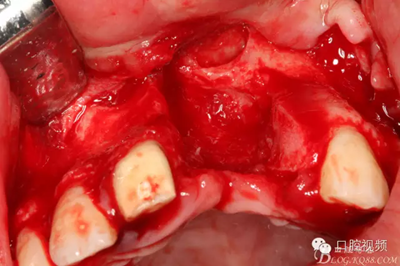

【原創(chuàng)博客】烤瓷橋下的悲劇-張東星